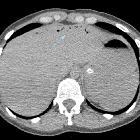

Systemic air

embolism and decompression illnes in a scuba diver.. Gas in the inferior vena cava in a upper level, shortly before the outlet in the right atrium.

embolism and decompression illnes in a scuba diver.. Arrow shows gas bubbles in some portal branches for the left hepatic lobe.